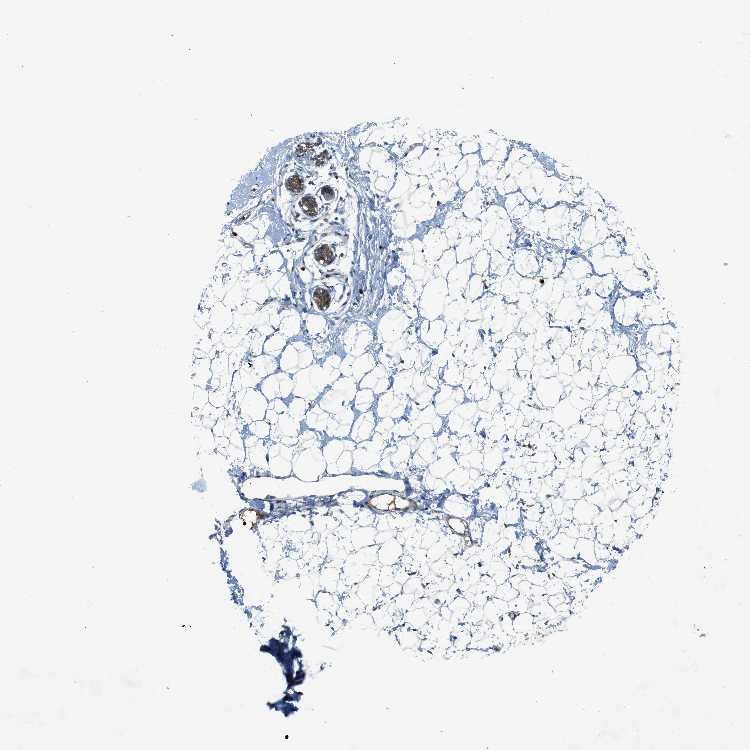

BREAST - Antibody stainingi

Antibody staining in the annotated cell types in the current human tissue is reported as not detected, low, medium, or high, based on conventional immunohistochemistry profiling in selected tissues. This score is based on the combination of the staining intensity and fraction of stained cells.

Each image is clickable and will lead to virtual microscopy that enables deeper exploration of all samples and also displays staining intensity scores, fraction scores and subcellular localization as well as patient and tissue information for each sample.

Antibody HPA014657

Adipocytes Not detected

Glandular cells Medium

Myoepithelial cells Low